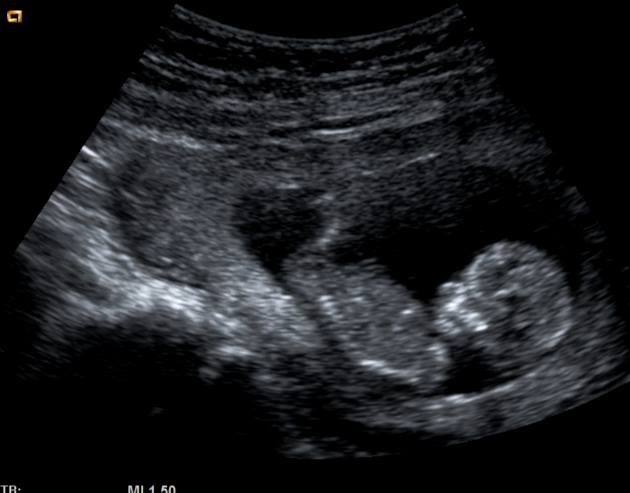

I can see a big difference in the skullshape, when I look at my sons u/s and this baby.

Here's my son, same term 12w5d

my guess is girl